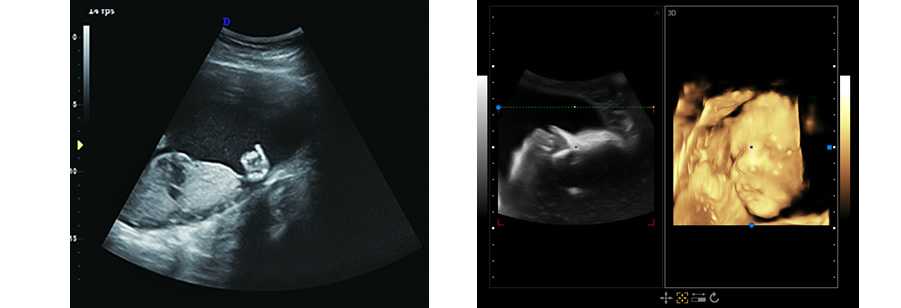

DW-CE780推車式全數字彩色多普勒超聲診斷儀

DW-T6

清晰圖像 觸手可及

DW-T6全身應用型彩色多普勒超聲診斷系統,采用全新的技術平臺,基于安全、穩定的操作系統從容應對各種突發狀況; 高性能、低功耗工控解決方案,保證更佳圖像性能的清晰呈現。高亮度、高分辨率彩色醫用液晶顯示器;高靈敏度超大觸摸屏,讓醫生在臨床應用中享受更多的操作樂趣。

立體光源成像 胎兒容貌實時顯示